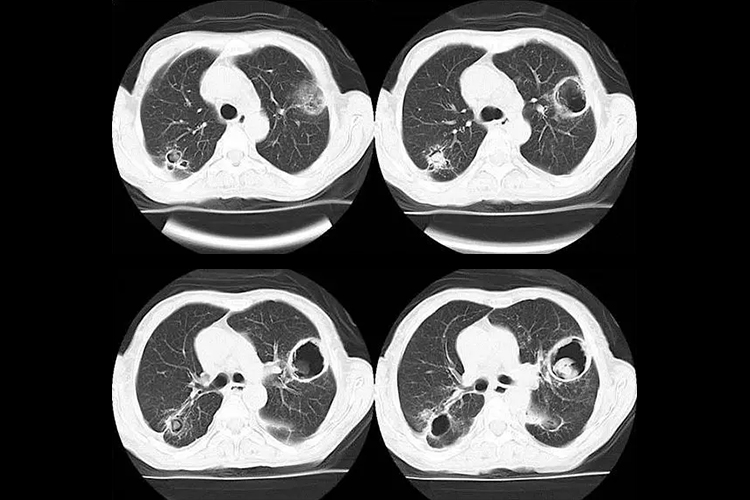

CT表现为孤立的和多发的结节性浸润,外周密度低于结节中心,高于正常肺组织,呈日晕样环状阴影称为晕轮征。疾病中、晚期由于梗死肺组织的收缩可形成空洞,典型者会有新月形空气征。